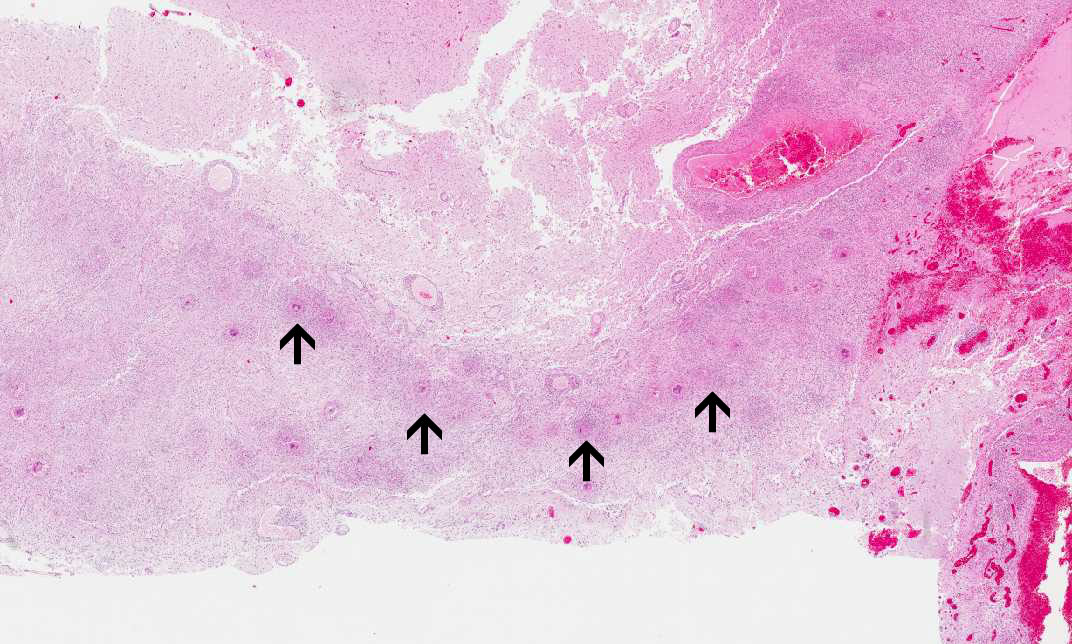

Hematoxylin & eosin

Area 4: In this image, you can see numerous granulomas (arrow) lining along the dura.

• In Slide #1, the salient pathologic change here is a necrotizing granulomatous inflammation of the leptomeninges associated with foreign body type giant cells and round inclusions that are morphologically consistent with Coccidiodes species. These organisms can be well demonstrated by PAS stain (see below). Note that there is fibrotic thickening of the leptomeninges (outlined by the arrows). The granulomas are only accompanied by a small amount of lymphocyrtes. Note that the granulomas are limited to the meninges.